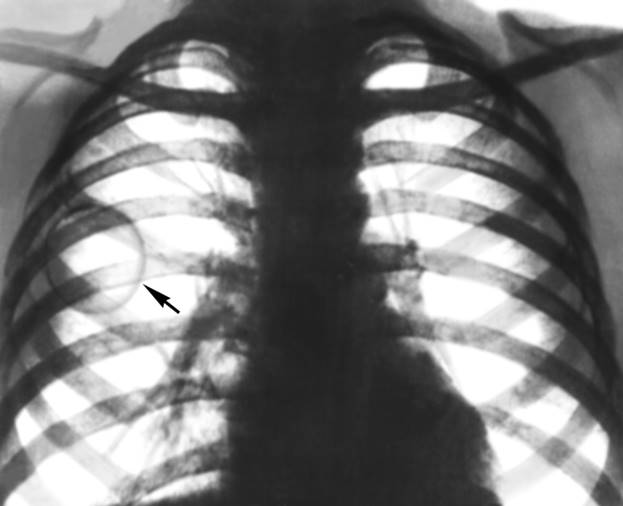

Кольцевидная тень в легочном поле. О синдроме кольцевидной тени в легочном поле следует думать лишь в том случае, если на снимках в 2 проекциях (прямой и боковой) имеется замкнутое кольцо. Анатомической основой данного синдрома являются полости в легочной ткани (абсцесс легких, поликистоз, распавшийся периферический рак легкого).

Рис. 9а). Обзорная рентгенограмма грудной клетки ребенка с врожденной воздушной кистой правого легкого в прямой проекции: кольцевидная тень кисты указана стрелками.